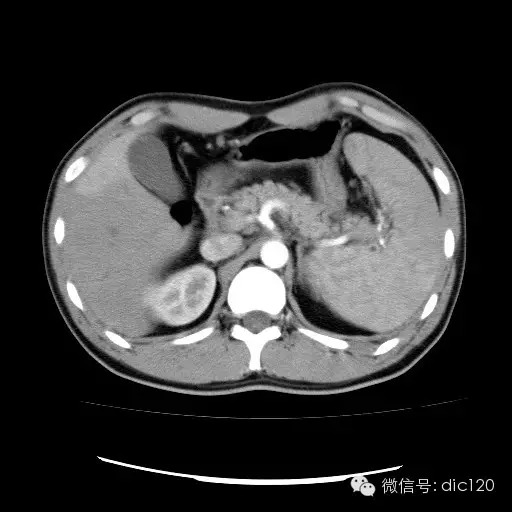

| 影像表现及分析: | 影像表现:动脉期扫描肝右叶紧贴边缘见一过性楔形高密度强化区,边界清,边缘平直,临近血管走形自然,门静脉期期恢复正常肝实质密度,延迟保持与肝实质密度一致。 |

| 疾病总结: | 正常肝脏的双重血供并非2个独立系统,两者之间有许多交通吻合,包括①肝窦间通路.②脉管间途径.③血管丛途径,即胆管周围血管丛途径.当肝脏发生血供障碍时,通过神经一体液因素的调节这些交通吻合支开放,双重供血发生血流量的变化甚至血流方向的改变.肝脏的这种”一过性”灌注异常在SCT表现为肝动脉期一过性肝实质强化(THPE).一过性肝实质强化差异是SCT增强扫描于肝动脉期表现的肝脏一过性灌注异常,大多数情况下它反映了局部肝脏双重血供的重新分布,即局部肝实质门静脉或肝静脉血流量减少,肝动脉血流量增多或为肝动脉门静脉分流或局部肝脏的变异或迷走血供所致。典型CT表现为肝动脉期一过性楔形或三角形高密度强化区,边缘平直,常位于肝脏边缘部位,其中血管走行正常,门静脉期恢复为正常肝实质密度。放射学医师应加强对一过性肝实质强化CT表现的认识。 |